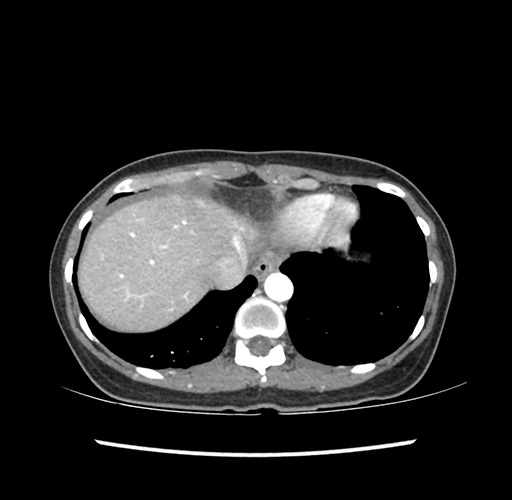

Imaging Analysis

Look through the patient's CT scan to identify any areas of concern for the necessary procedure.

Based on your CT findings, which issue(s) would give reason for "planned slowing down moment(s)" in this case?